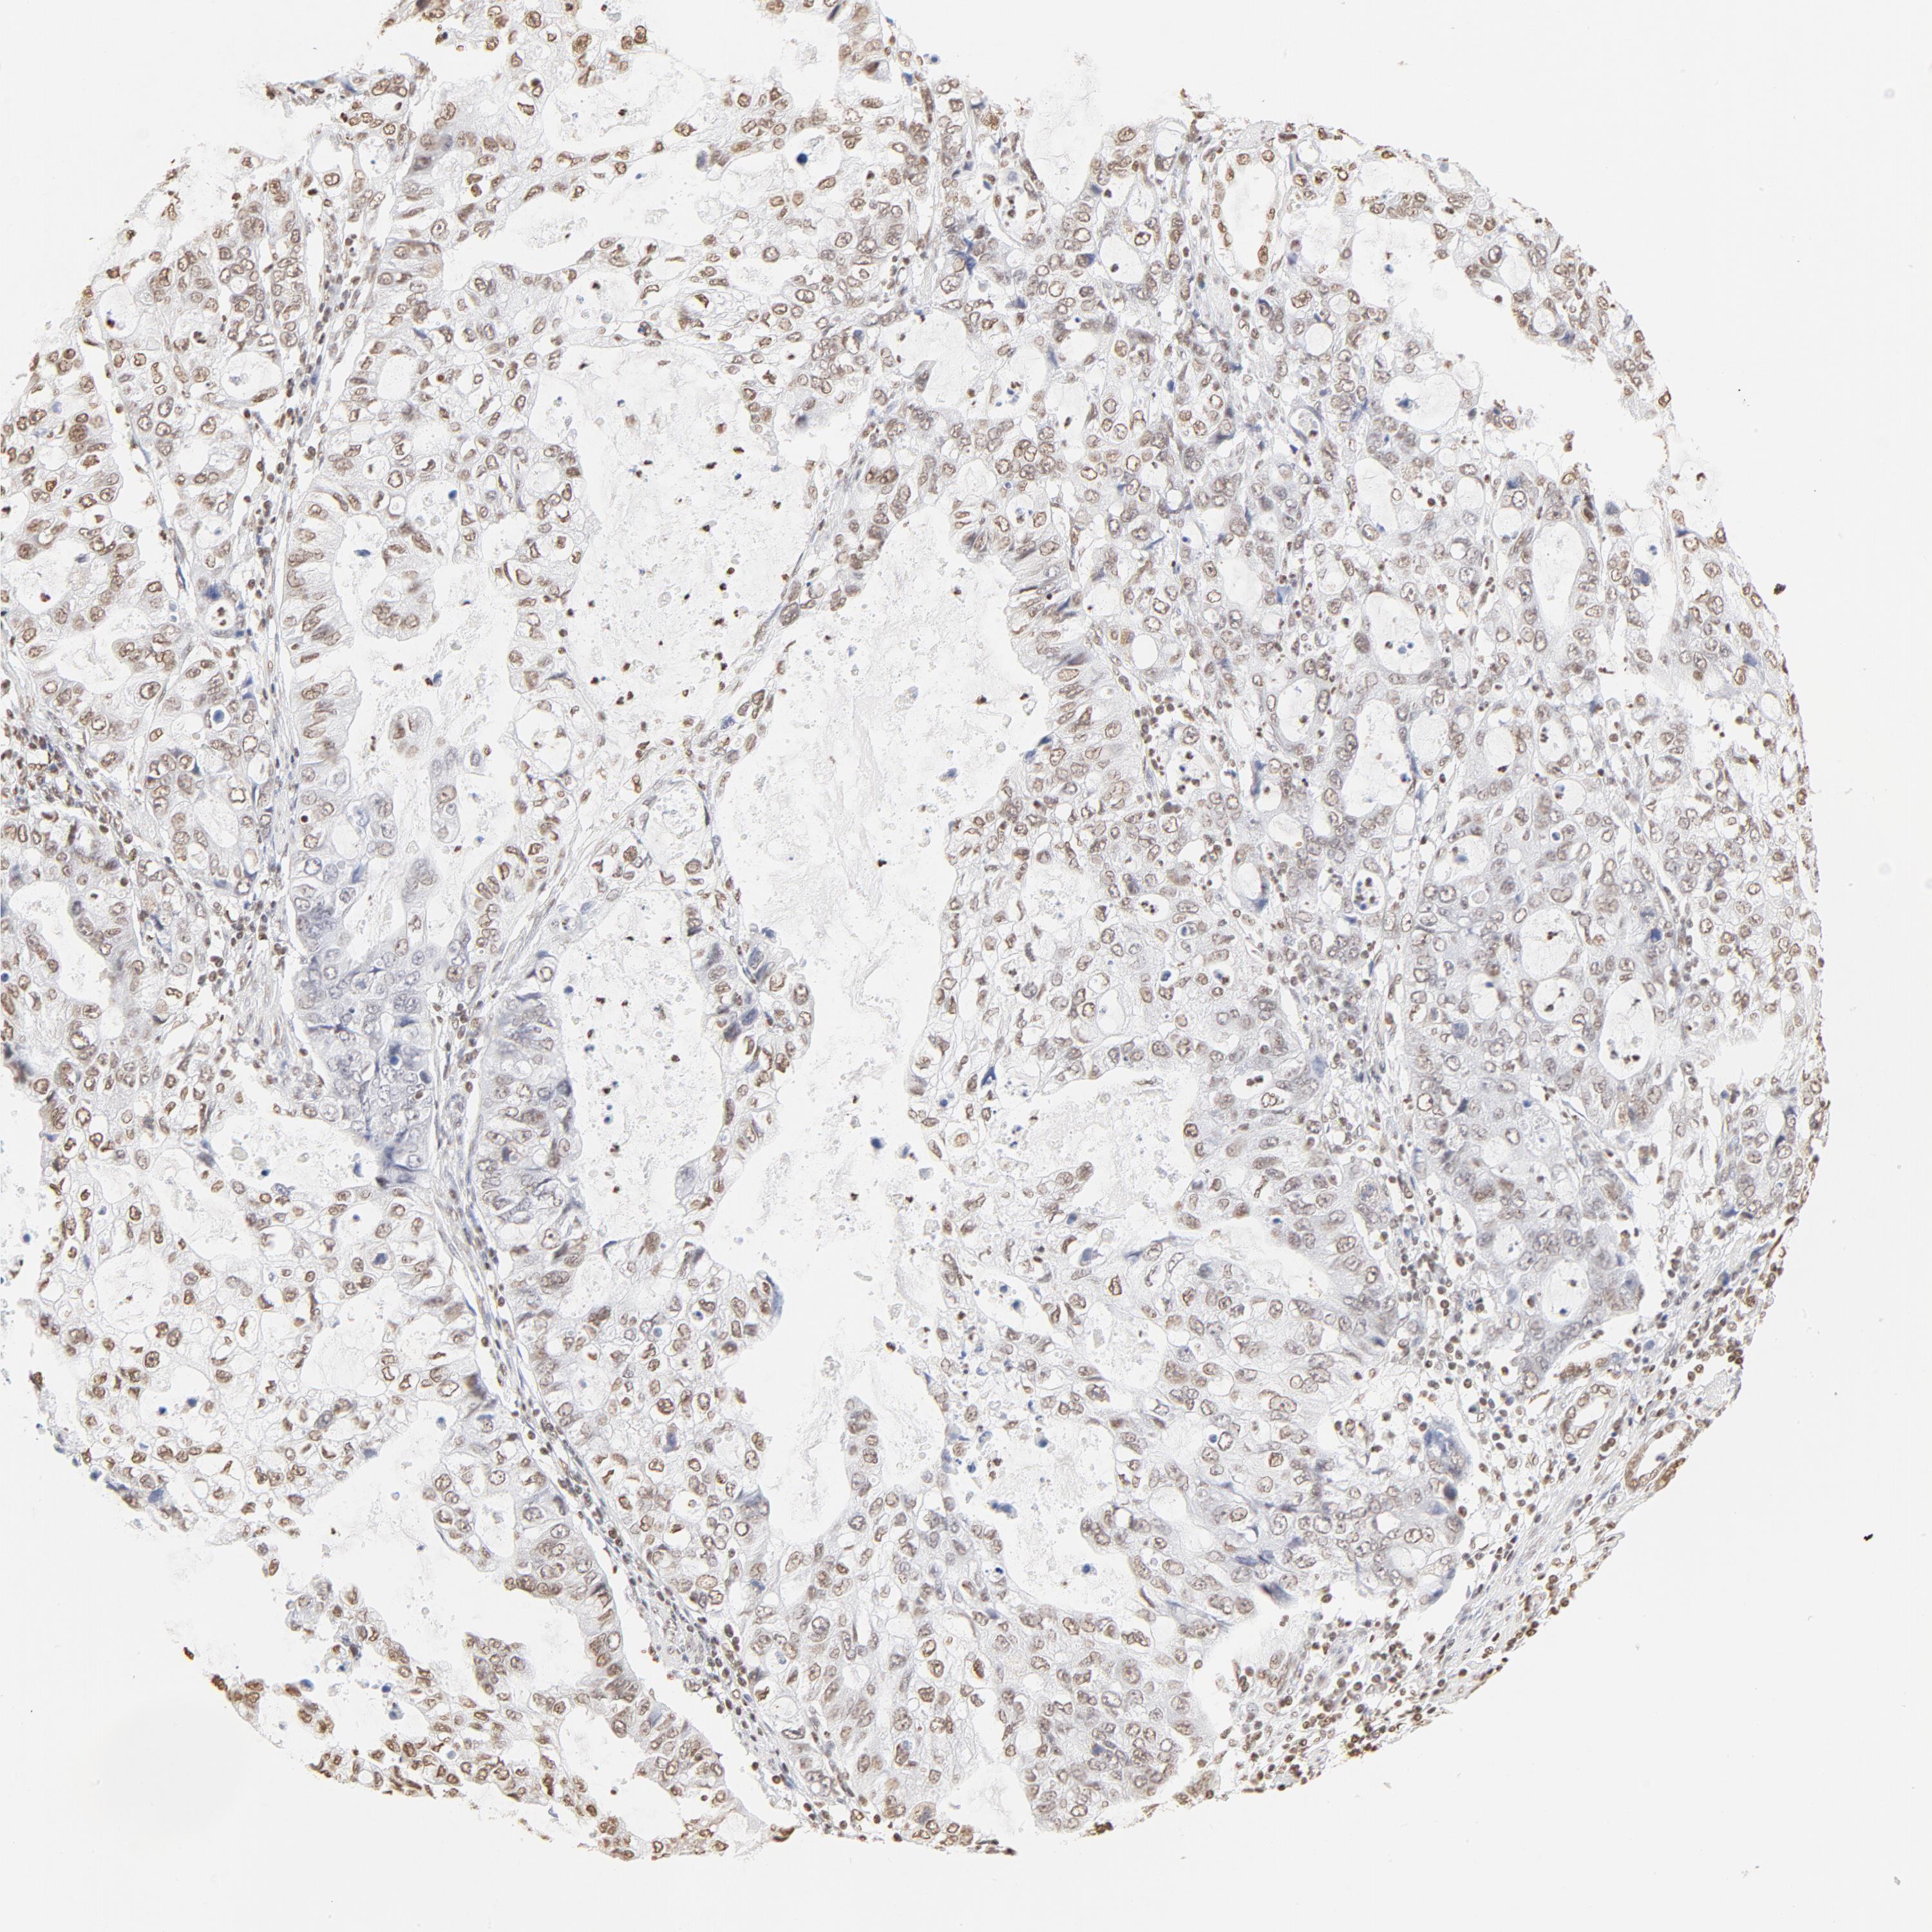

STOMACH CANCER - Protein expressioni

A mouse-over function shows sample information and annotation data. Click on an image to view it in a full screen mode. Samples can be filtered based on level of antibody staining by selecting one or several of the following categories: high, medium, low and not detected. The assay and annotation is described here.

Note that samples used for immunohistochemistry by the Human Protein Atlas do not correspond to samples in the TCGA dataset.

Antibody stainingi

Antibody staining in the annotated cell types in the current human tissue is reported as not detected, low, medium, or high, based on conventional immunohistochemistry profiling in selected tissues. This score is based on the combination of the staining intensity and fraction of stained cells.

Each image is clickable and will lead to virtual microscopy that enables deeper exploration of all samples and also displays staining intensity scores, fraction scores and subcellular localization as well as patient and tissue information for each sample.

Antibody HPA003444

Staining

High

Medium

Low

Not detected

Intensity

Strong

Moderate

Weak

Negative

Quantity

>75%

75%-25%

<25%

None

Location

Nuclear

Cytoplasmic/membranous

Cytoplasmic/membranous,nuclear

Adenocarcinoma, NOS